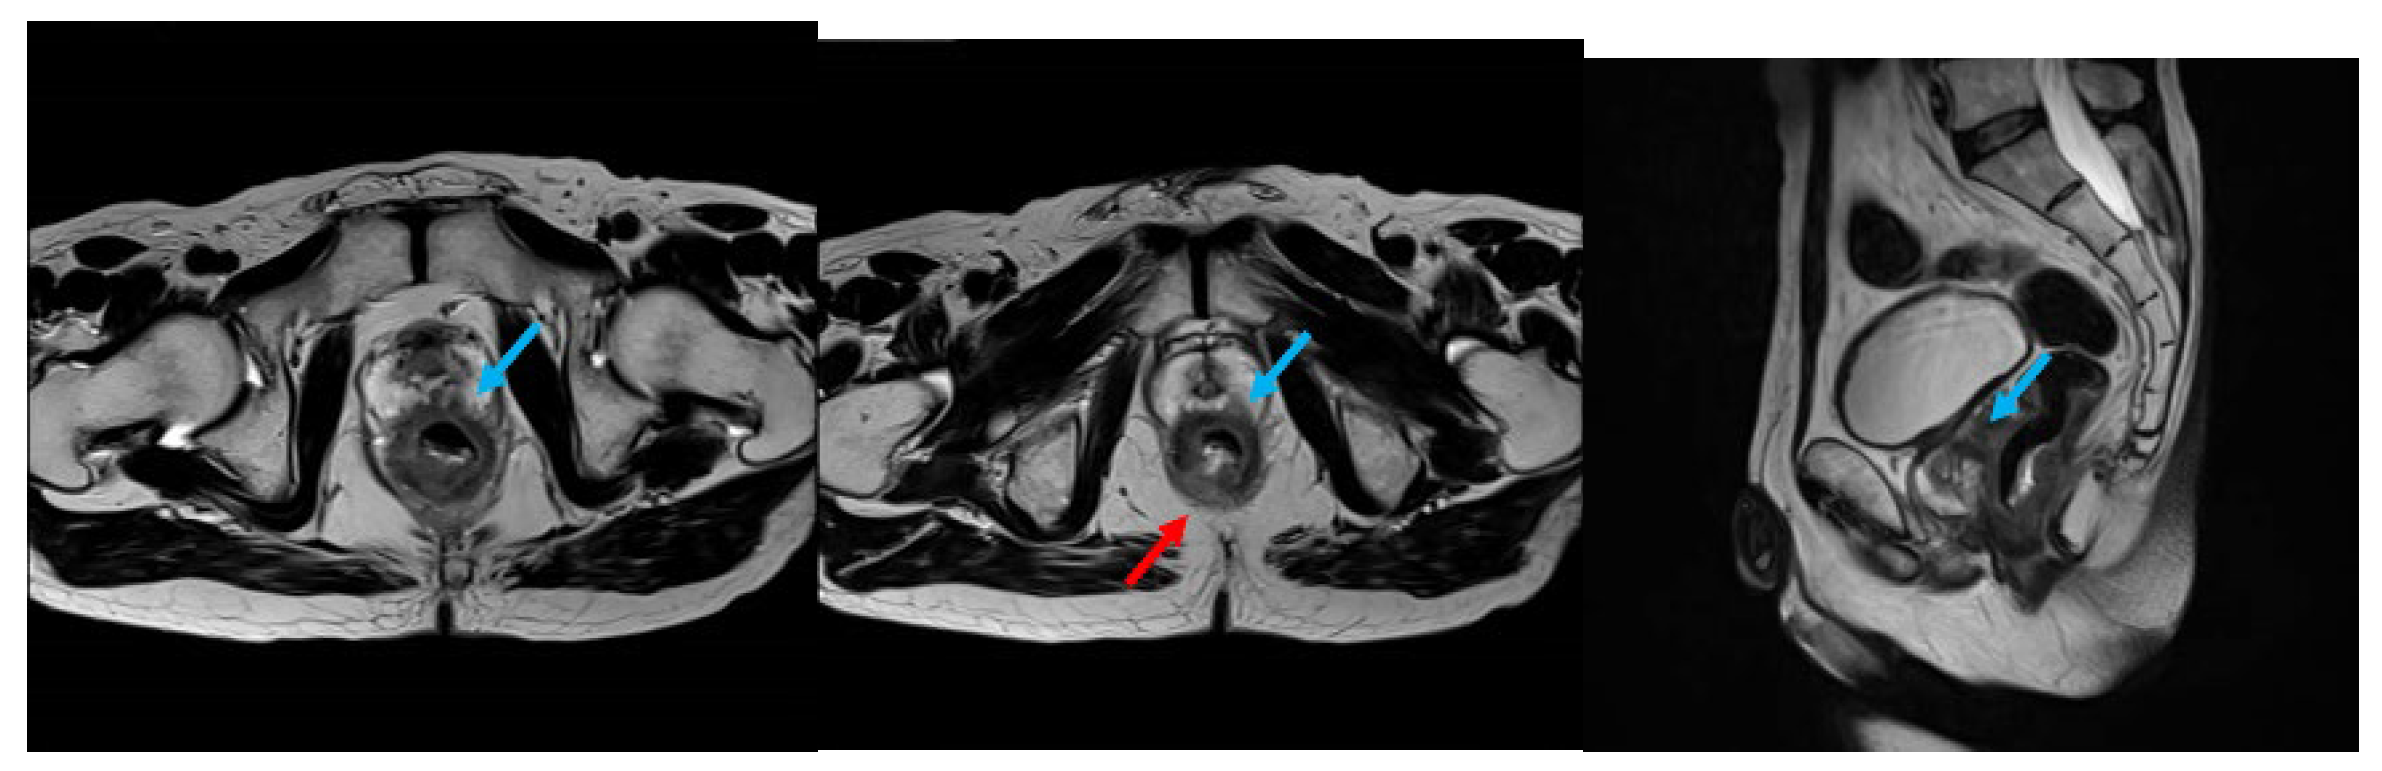

For staging purposes, contrast-enhanced computed tomography (CT) and magnetic resonance imaging (MRI) were performed. Although no distant metastasis or regional/lateral lymph node involvement were detected, the tumor appeared to extensively invade the prostate and the levator ani muscle (Figure 1). Based on these findings, the clinical stage was determined to be cT4b (prostate, levator ani muscle), N0, M0, corresponding to stage Ⅱc.

Figure 1. Preoperative T2-weighted MRI revealed a circumferential tumor in the lower rectum, with suspected invasion into the prostate (blue arrow) and levator ani muscle (red arrow).